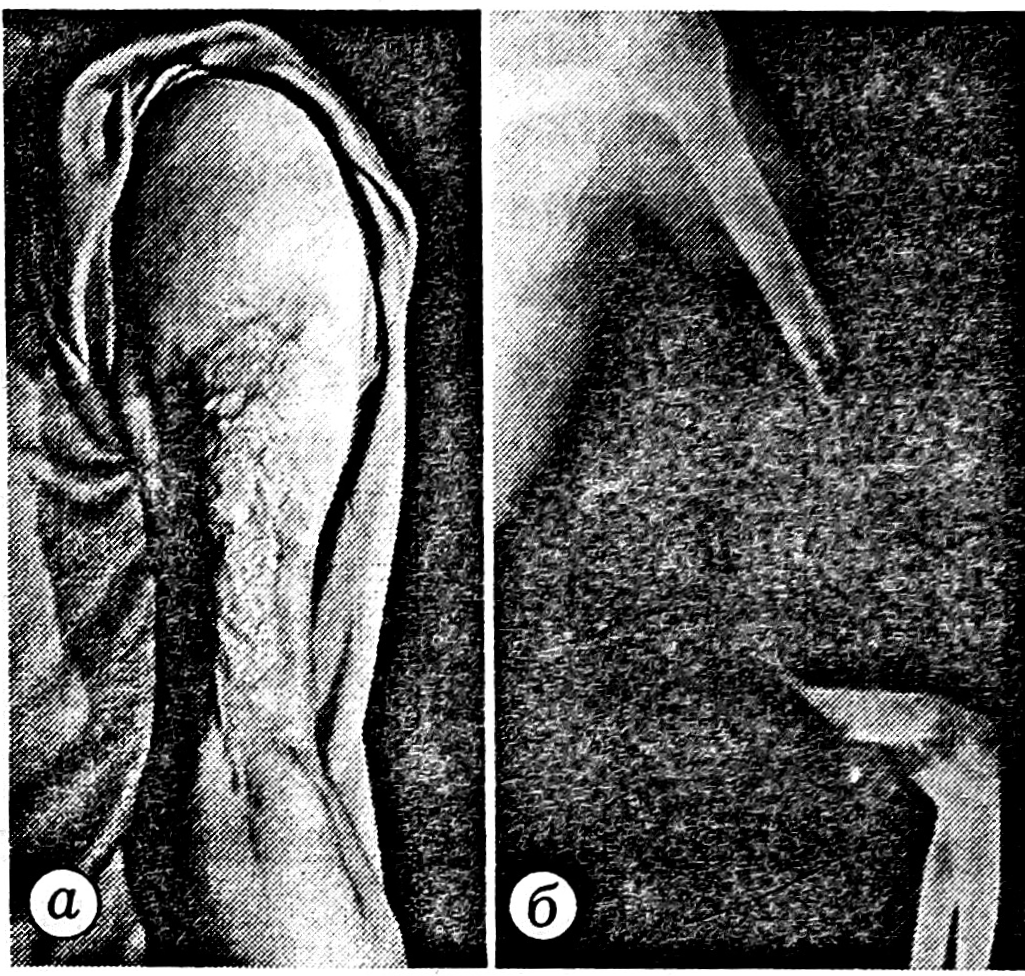

Больная С., 33 лет, поступила в клинику микрохирургии и травмы кисти ЦИТО с дефектом левой плечевой кости, мягких тканей и кожного покрова плеча (кожа сохранилась только по его внутренней поверхности на участке шириной 6 см), окклюзией плечевой артерии в нижней трети плеча (рис. 1). Травму получила в Ливане — минно-взрывное ранение.

Рис. 1. Больная С. при поступлении.

а — внешний вид поврежденного сегмента; б — рентгенограмма плеча: обширный дефект кости; в — ангиограмма: повреждение плечевой артерии в ее нижней трети, кровоток коллатеральный.